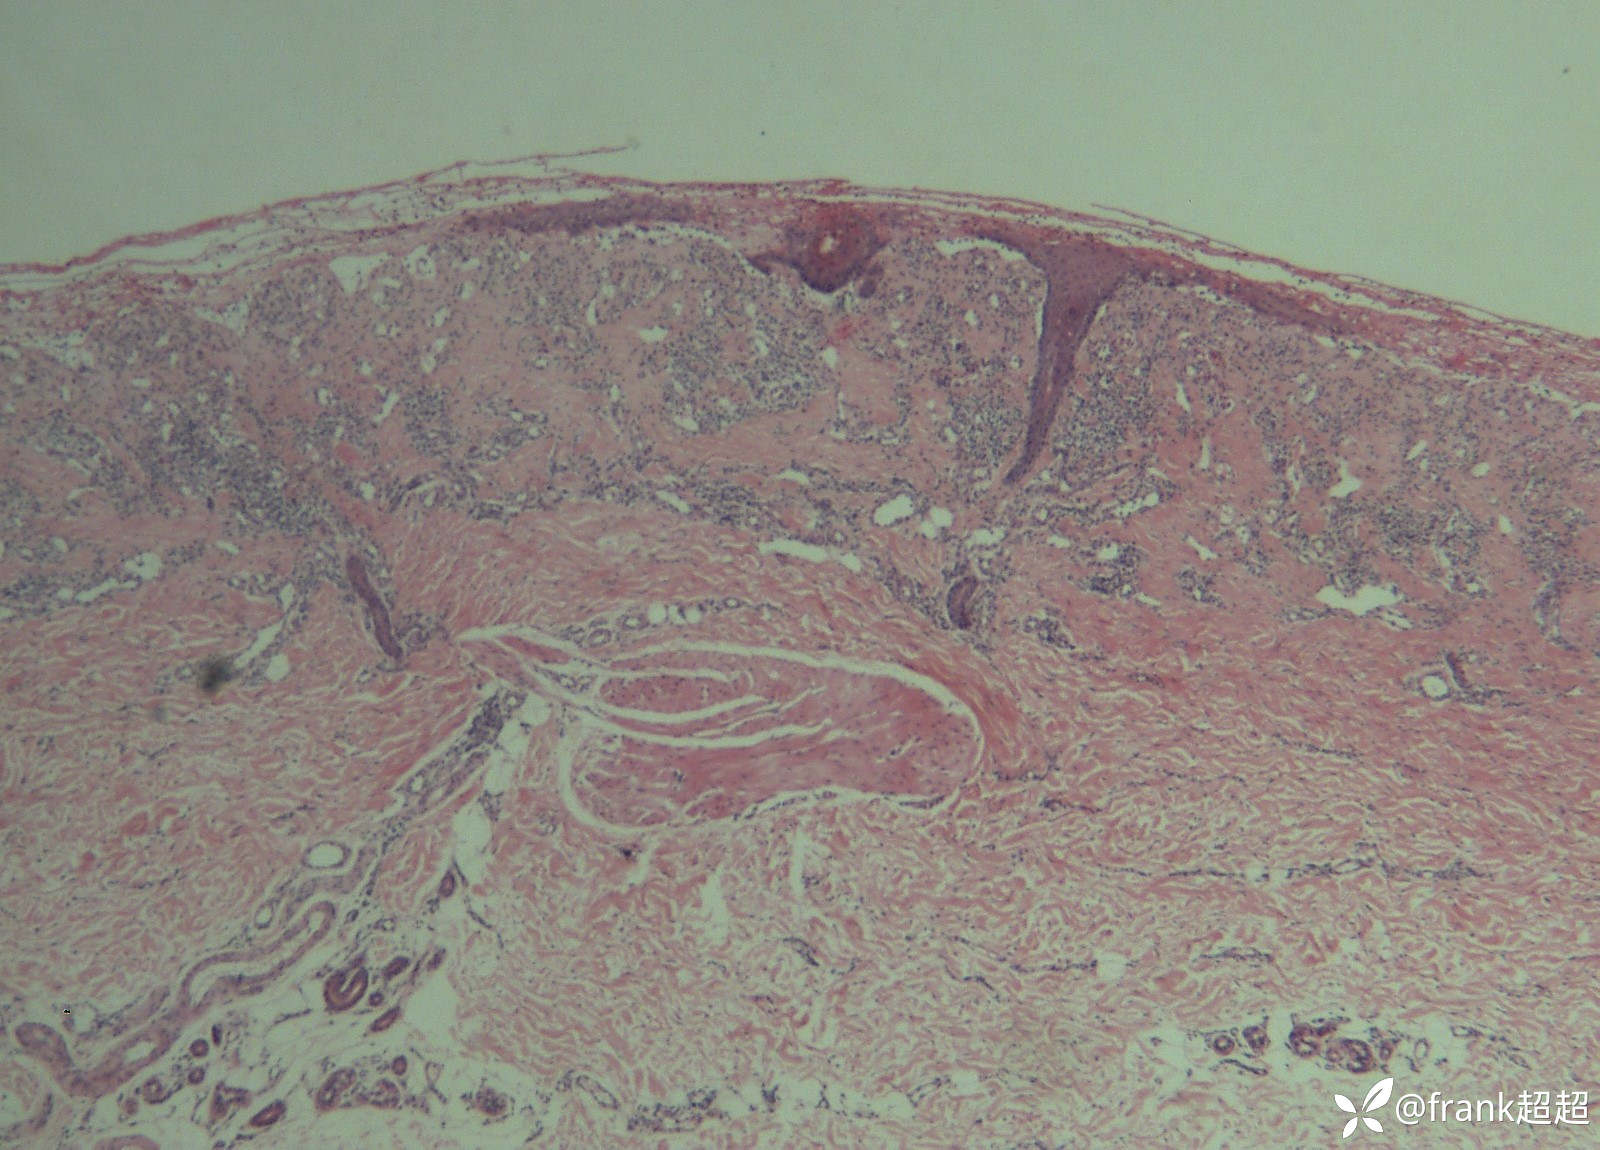

病理:

病理提示:表皮下水疱形成,疱内可见纤维蛋白样物质及少许嗜酸性粒细胞,真皮浅层血管周围可见淋巴细胞及少许嗜酸性粒细胞为主的炎症浸润。